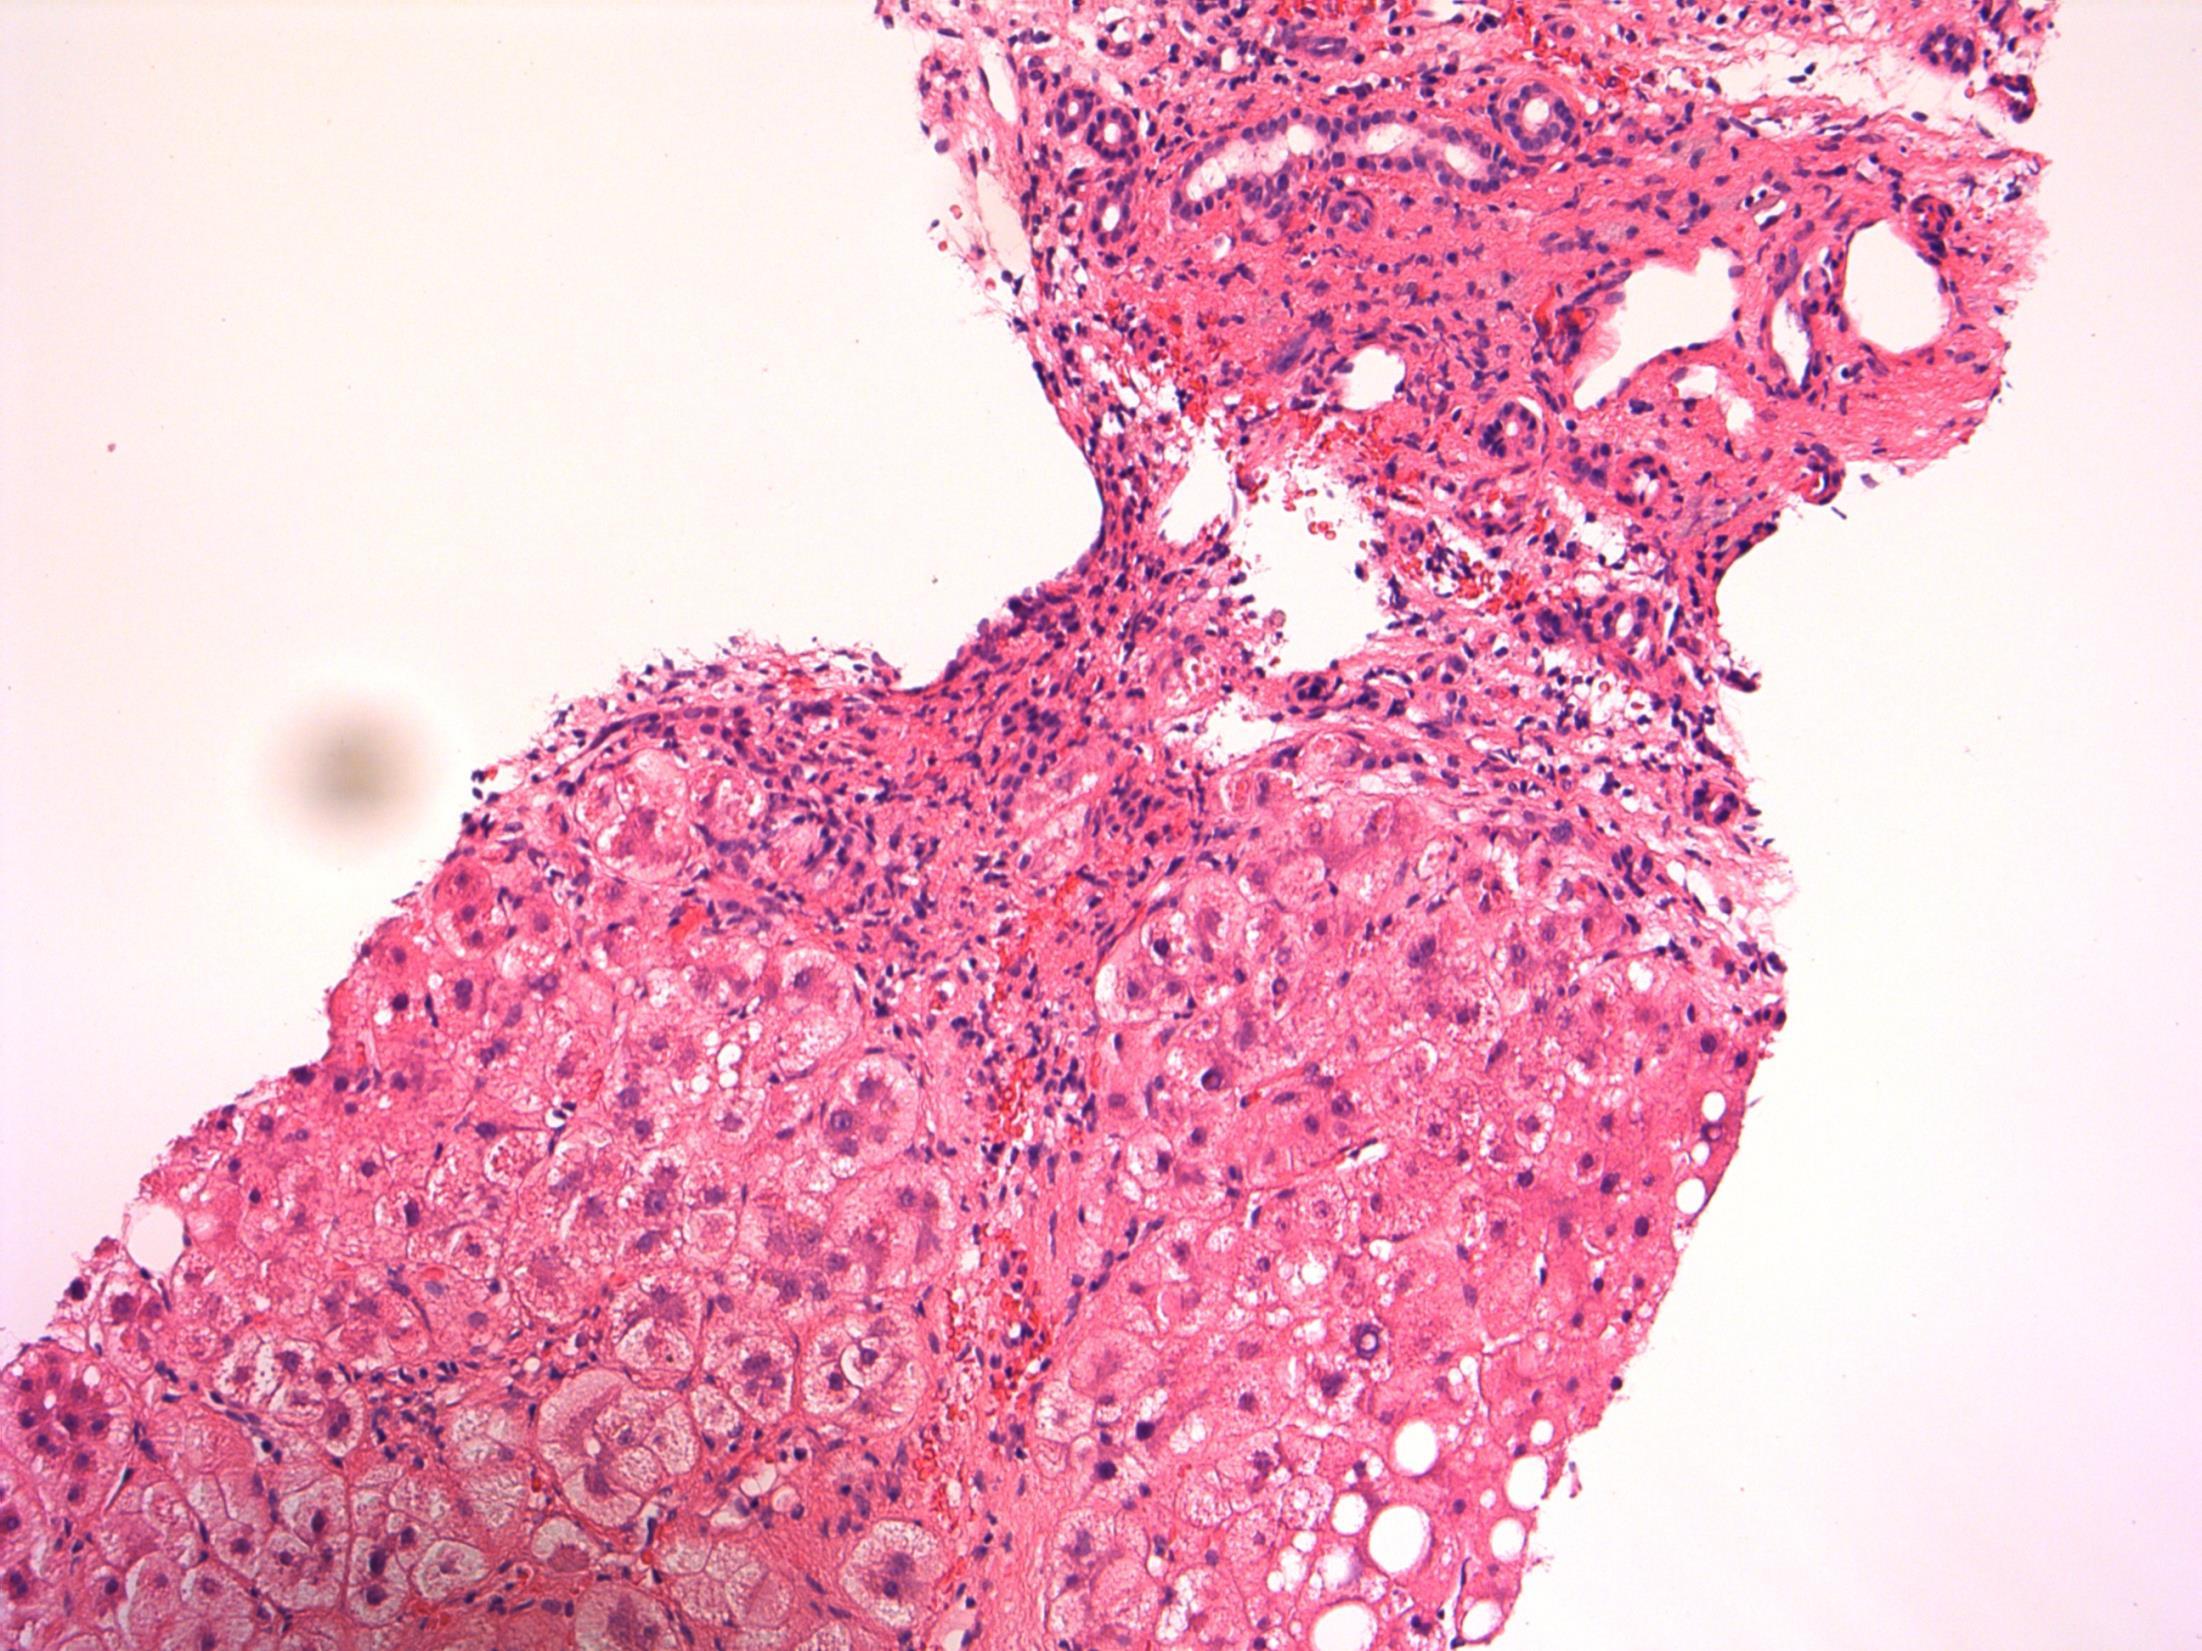

Focal lactational change

Description: Dilated acini with secretions, vacuolated cytoplasm and hobnail appearance. Microcalcifications associated. No evidence of DCIS or invasive malignancy.

Diagnosis: Lactational change with microcalcifications (B2)

Plan: Correlate with radiology and clinical examination at the MDT Correlate with any cytology, if perormed.

Comments:

• Biopsied because of microcalcifications .

• Usually seen associated with pregnancy/breast-feeding, unlikley in this age as 50 years old.

• Can be seen in non-pregnant (even nulliparous) women – usually focal, no clinical significance, like in this case.

• Can have associated ADH/DCIS, not present in this case.

• No further treatment required.

3.5 Importance of radiological correlation at MDT 3.0 B coding, significance 2.5 Description with diagnosis / DD 2.0 Other benign diagnosis with no mention of lactational change 1.5 Atypical diagnosis 1.0 Malignant diagnosis Case